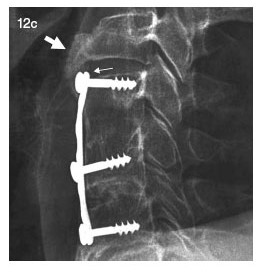

Continúo atada a la cama, en el falso techo he dibujado nubes, corazones y hasta dinosaurios. A pesar de la recuperación, Jorgito y Marianela, el equipo de neurocirujanos, deciden operarme para evitar una re- luxación.

Durante el pase de visita anuncian que harán una disectomía con injerto óseo autólogo y fijación con láminas y tornillos, y yo pido que traduzcan a un idioma entendible para mí.

- Es una operación trabajosa y complicada como todas -afirma Jorgito- te vamos a quitar un pedacito de hueso de la cadera, para ponerlo en la cervical fijado con una lámina y tres tornillos.